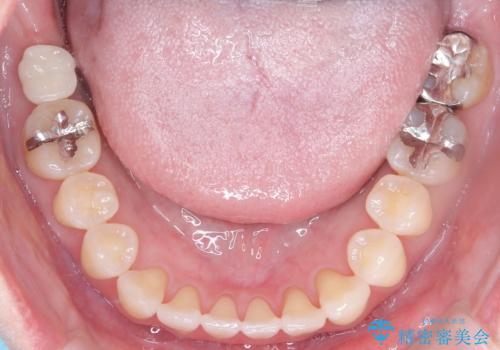

- 上の前歯の捻れと、前歯で物が噛めないことを主訴に来院されました。

前歯の翼状捻転とオープンバイト傾向だったため、インビザラインにて矯正を行いました。右下の奥歯は保存不可だったため、抜歯を行いインプラントにて修復を行なっています。

翼状捻転はインビザラインでは苦手とする動きですが、ここまで綺麗に治すことができました。